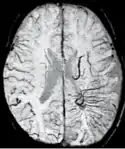

Gradient recalled echo (GRE) imaging is the conventional way to detect hemorrhage in CAA, however SWI is a much more sensitive technique that can reveal many micro-hemorrhages that are missed on GRE images.[7] A conventional gradient echo T2*-weighted image (left, TE=20 ms) shows some low-signal foci associated with CAA. On the other hand, an SWI image (center, with a resolution of 0.5 mm x 0.5 mm x 2.0 mm, projected over 8mm) shows many more associated low-signal foci. Phase images were used to enhance the effect of the local hemosiderin build-up. An example phase image (right) with yet higher resolution of 0.25 mm x 0.25 mm x 2.0 mm shows a clear ability to localize multiple CAA-associated foci.